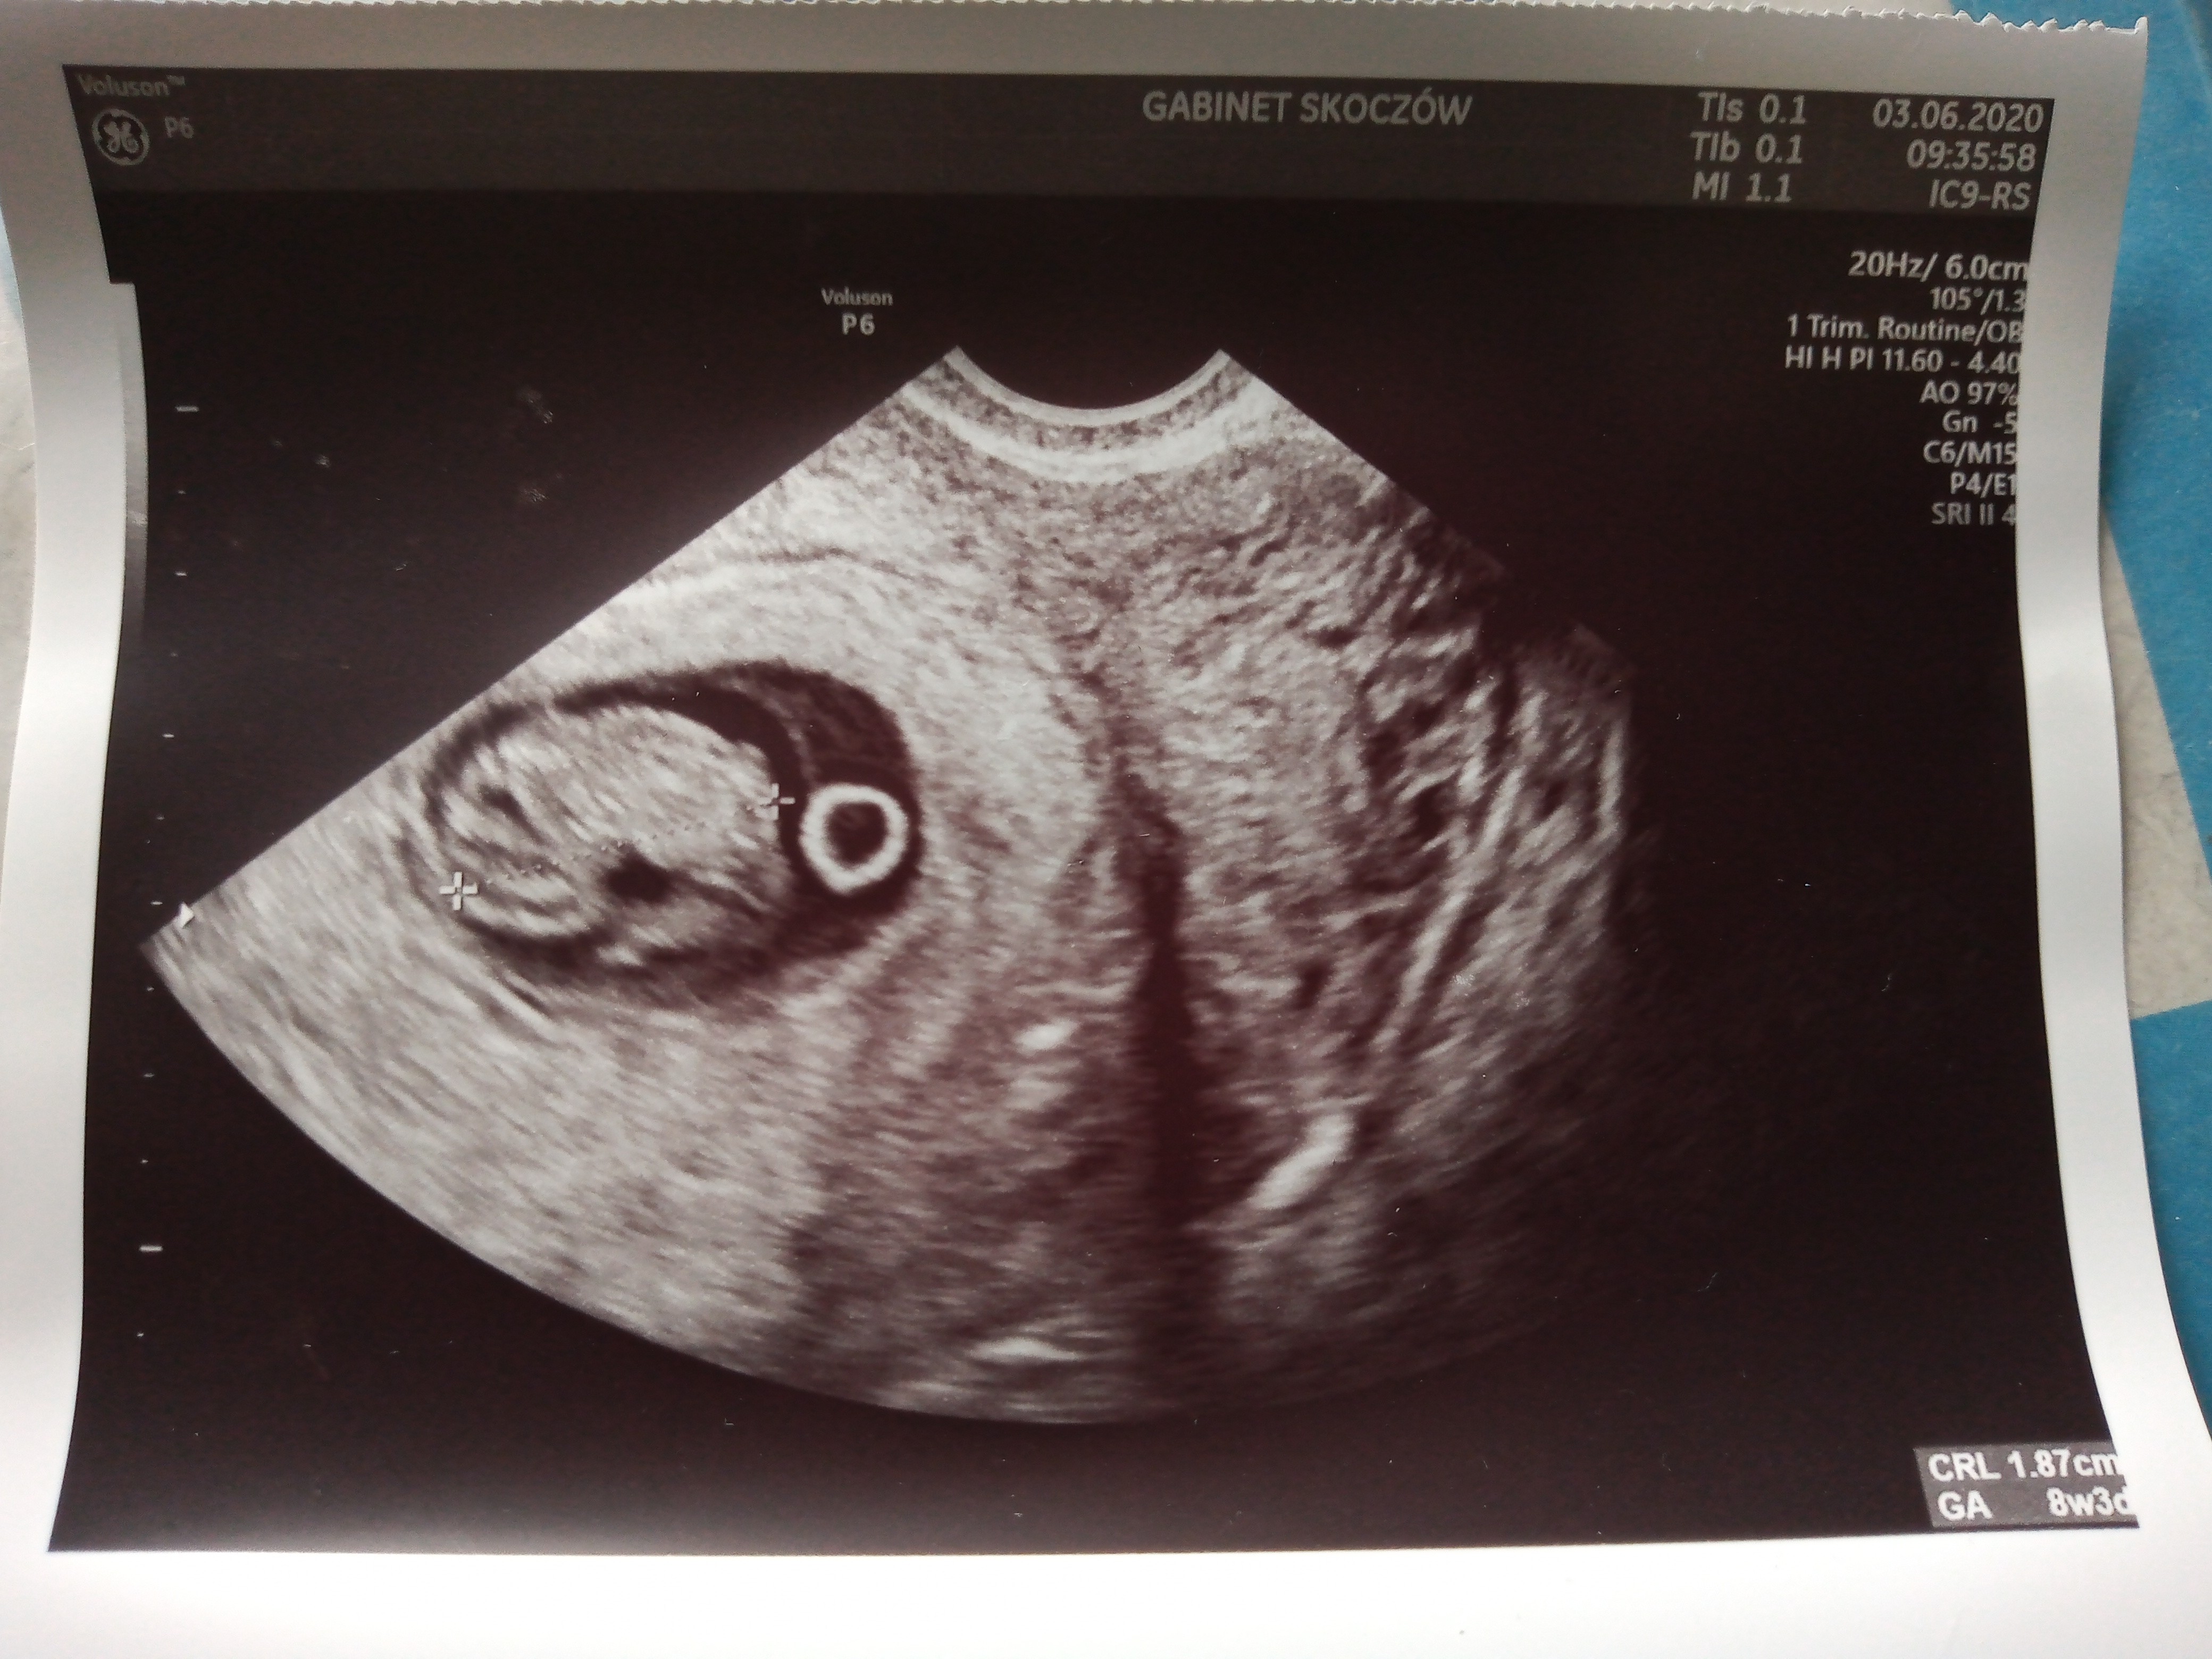

Proszę tutaj moje maleństwo ❤ . Śmiejemy się z ukochanym, że mały głodomor śpi już teraz na "lodówce". Jak to zobaczyłam że leży na pęcherzyku żółtkowy to padłam.super maluszki! ciekawe jak mój jutro będzie wyglądałma któraś zdjęcie z USG w 8tc? jestem ciekawa czego mogę się spodziewać

![]()

ale pięknie widać!Proszę tutaj moje maleństwo ❤ . Śmiejemy się z ukochanym, że mały głodomor śpi już teraz na "lodówce". Jak to zobaczyłam że leży na pęcherzyku żółtkowy to padłam.![]()